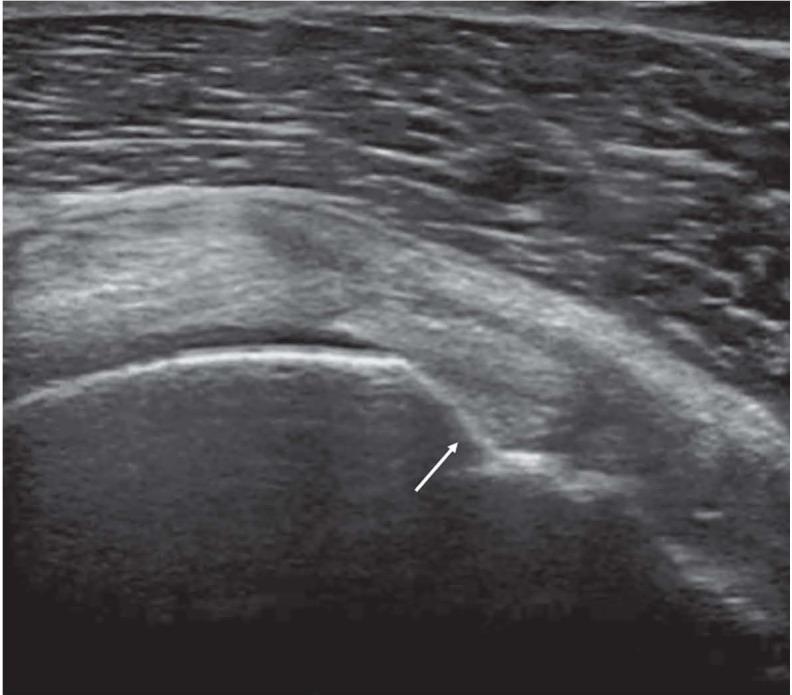

The aim of this is article is to provide an  imaging review of normal anatomy, most common anatomical variants and pathologies of the long head of the biceps tendon (LHB) encountered during the daily practice.

本文的目的是对日常实践中遇到的肱二头肌长头肌腱(LHB)的正常解剖结构、最常见的解剖变异和病变进行影像学综述。